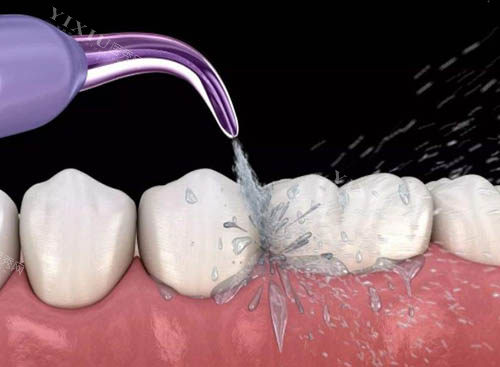

对于口腔常见问题,如龋齿、牙周炎等,爱雅口腔提供基础治疗。医生会进行检查,然后给出治疗建议。有患者反映,治疗后不适感得到缓解,日常口腔护理建议也比较实用。